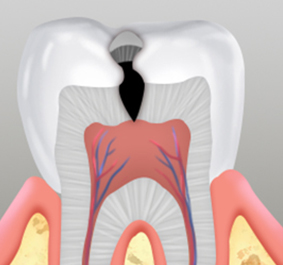

치아의 손상 정도가 심각하여 치아 내부 조직인 신경 혈관에 염증이 생긴 경우,

내부 조직을 제거한 후 치과용 충전재료를 충전한 후 크라운을 씌워 마감합니다.